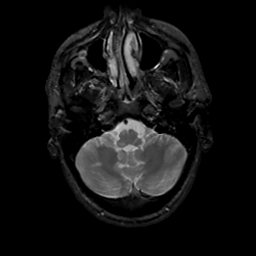

MR Study #16, June 23, 1991 -- Slice #9